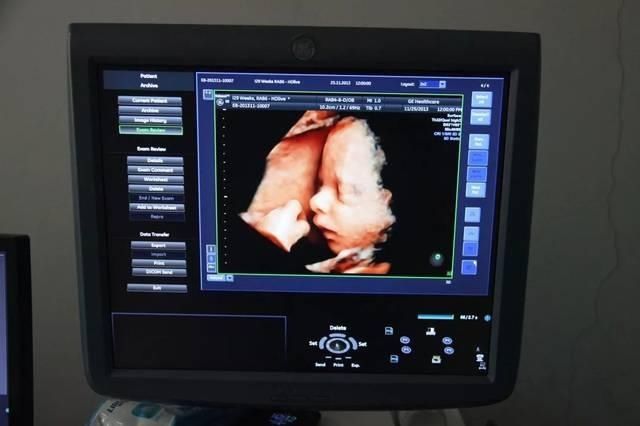

明星们怀孕比较常见的官宣招式就是晒B超单。

主要是因为怀孕的时候,B超检查是产检非常重要的一个项目,而很多妈妈也是通过B超来了解胎宝宝在妈妈子宫里面的各种情况。

加上得出来的B超单已经可以看得出孩子的五官。